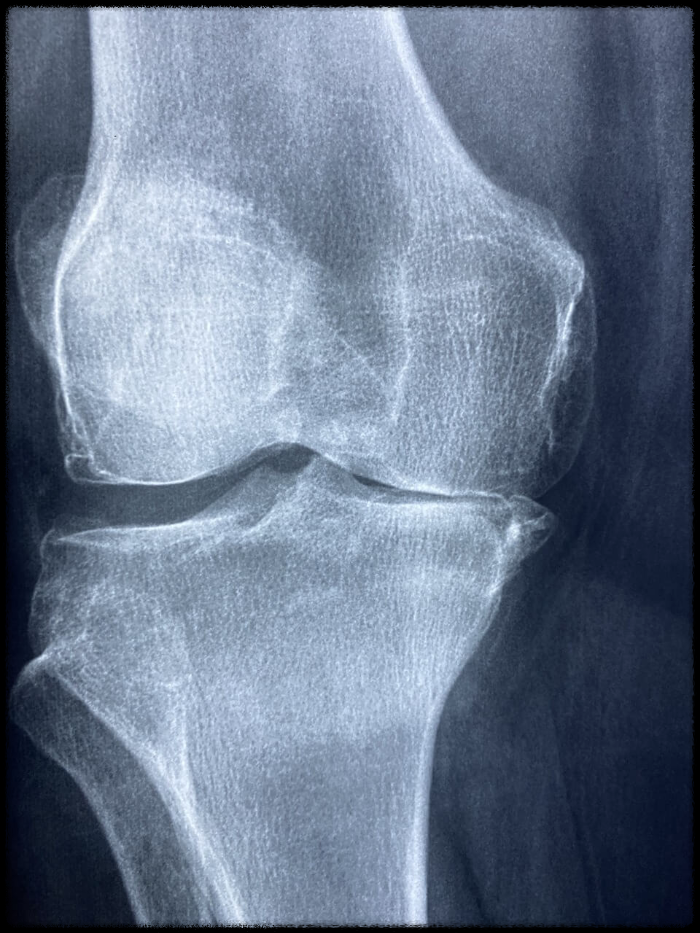

- 퇴행성관절염 증세가 악화되면 재생능력이 없는 연골이 닳게 되면 손상된 관절을 대신해 줄 특수 플라스틱으로 된

인공관절을 퇴행성관절염이 진행된 부위에 삽입하는 수술입니다.